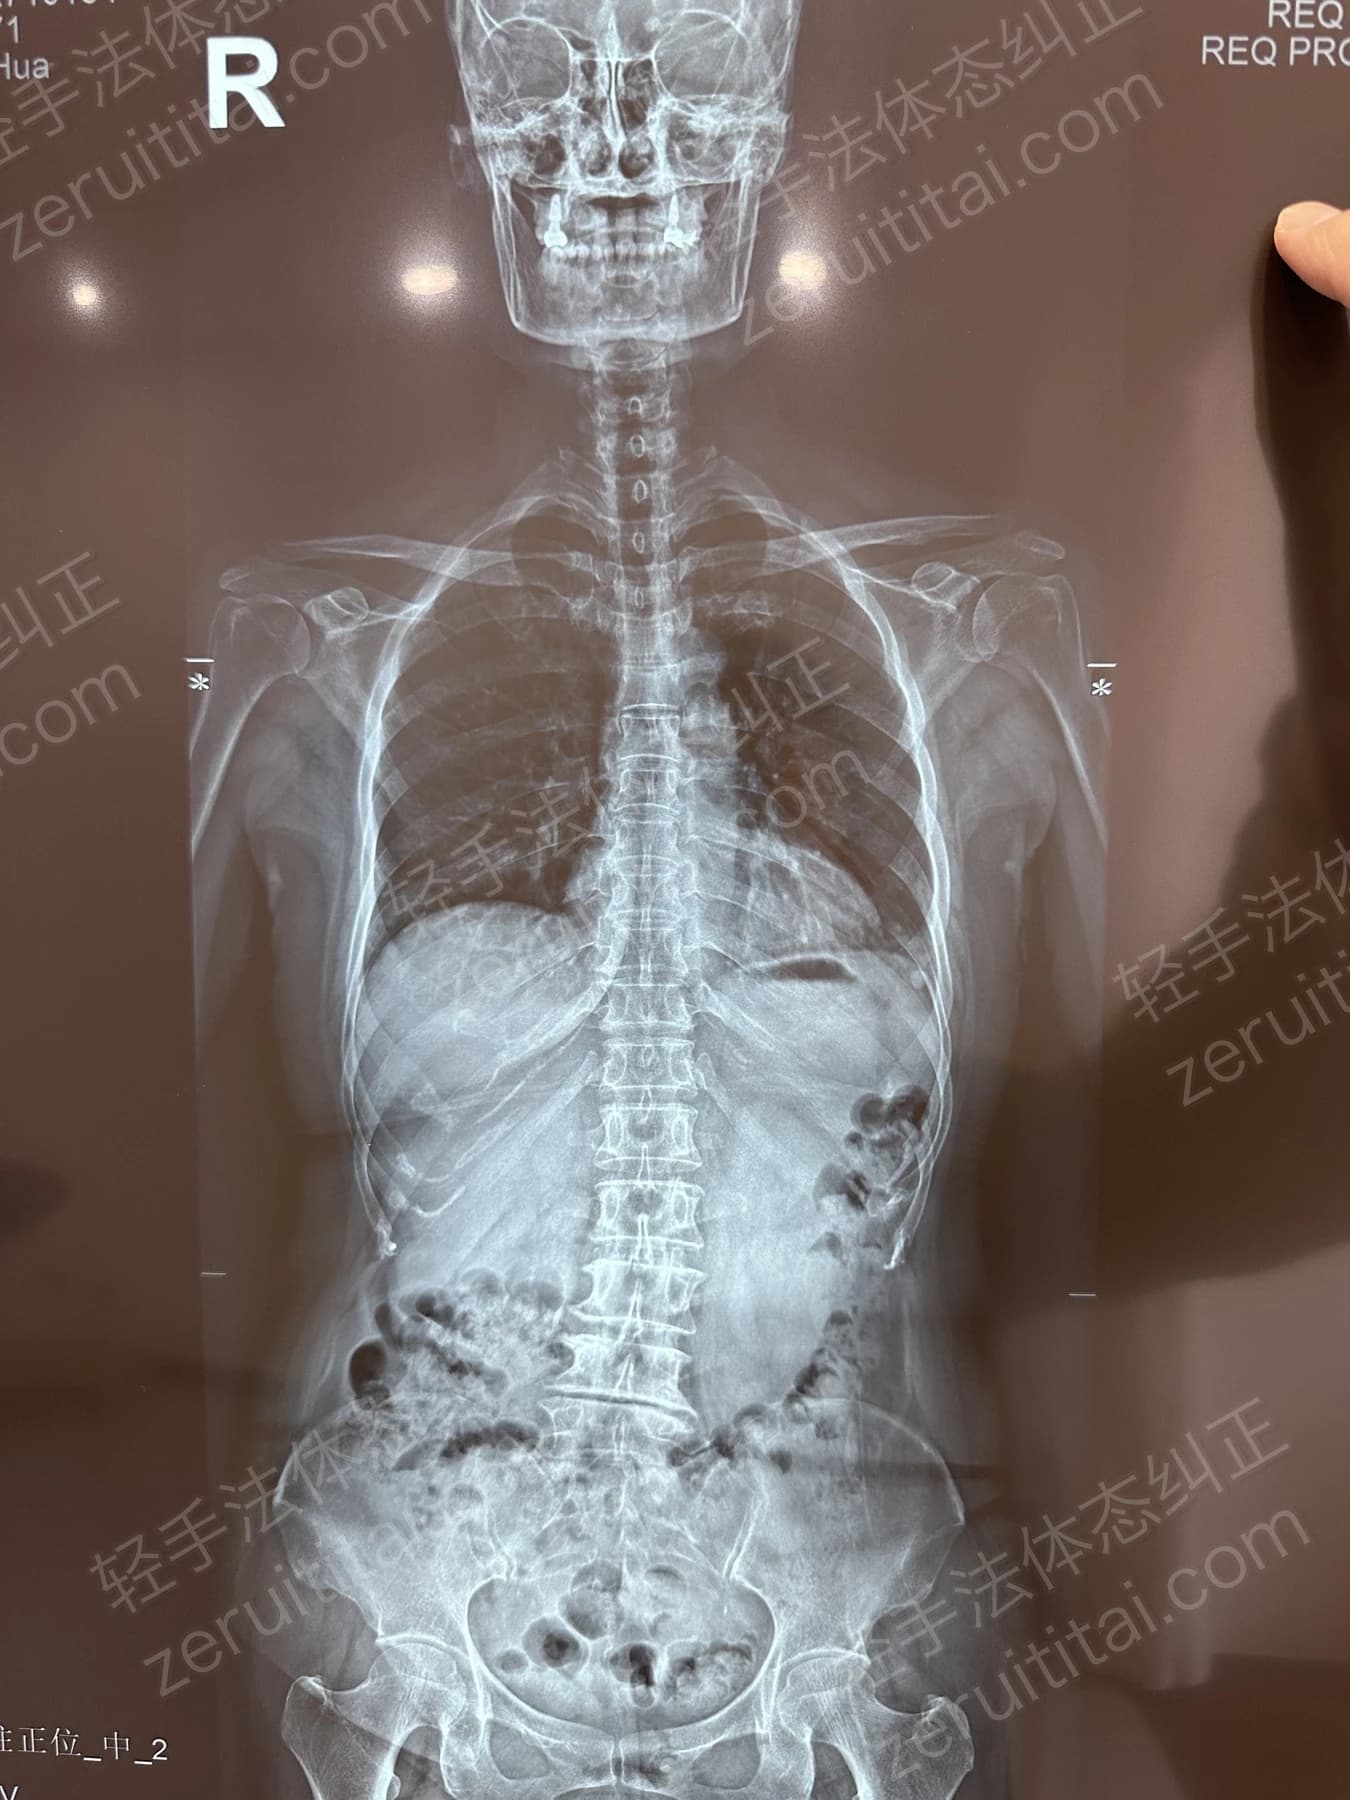

2022.06.27

第 1 次记录